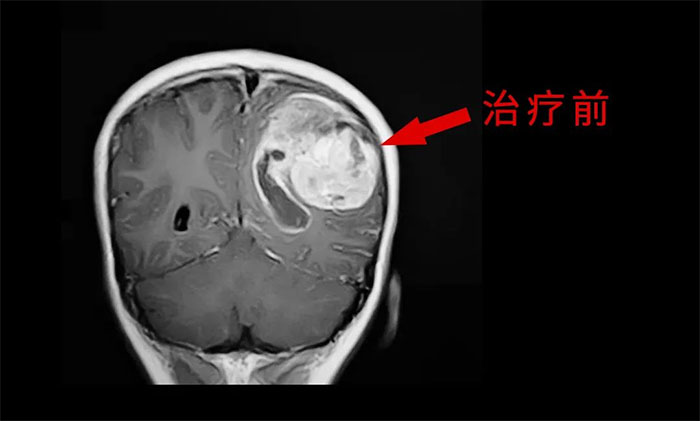

外科手术往往是胶质瘤治疗的第一步。手术原则是在最大范围安全切除(maximal safe resection)肿瘤的同时,保护神经功能区。以解除占位征象和缓解颅内高压症状;解除或缓解因脑胶质瘤引发的相关症状;获得病理组织和分子病理,明确诊断;降低肿瘤负荷,为后续综合治疗提供条件。

放、化疗等亦是不可或缺的重要治疗手段,高级别胶质瘤术后选择标准同步放、化疗可以取得显著的生存获益。

于耀宇主任特别指出,随着脑血管介入技术快速发展,脑胶质瘤术后超选介入化疗联合同步放疗的效用正逐渐为大家所认识。超选介入化疗,是利用微导管技术直接将药物通过供血动脉,灌注到颅内肿瘤组织区域,避免了传统口服或静脉注射药物,要经过全身代谢后才能到达肿瘤区域。可减轻全身毒性反应,延长化疗药在肿瘤内的滞留时间,更好地杀伤肿瘤细胞。